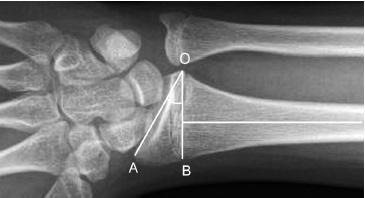

- The RUI enables the correlation to the length of the ulna and radius bones on radiographs in the frontal view. It is measured as the distance between two lines drawn in parallel, with one of them along the articular surface of the ulna, and the other at the level of the proximal surface of the sigmoid notch of the radius in the images in the frontal view (Fig. 4). On average, this indicator ranges from −2.5 mm to +3.1 mm [14].

Fig. 4. X-ray of the wrist joint in direct projection. Radioulnar index — the ratio of the lengths of the ulna and radius: a — the negative version of the index (normal version); b — neutral variant of the index (norm variant); c — positive version of the index

Zero variant, or neutral variant (the levels of the distal articular surfaces of the radius and ulna coincide); positive variant, or “ulna-plus’ (the articular surface of the ulna is located distal to the radius); negative variant, or “ulna-minus” (the articular surface of the ulna is located proximal to the radius), were used.